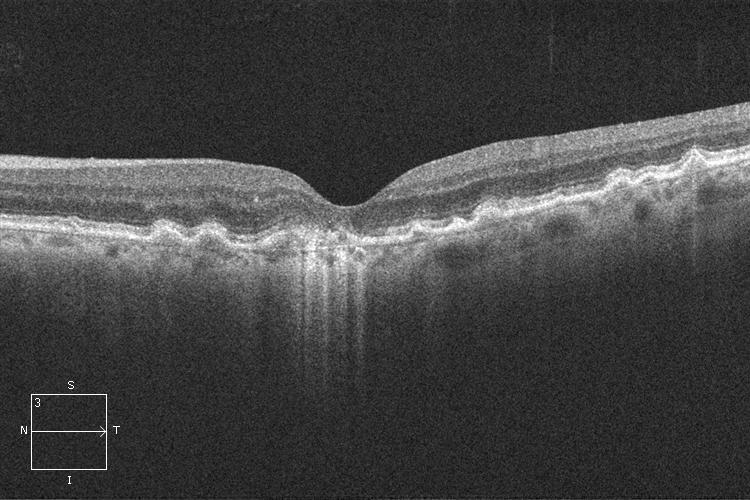

- La Degeneración Macular Asociada a la Edad (DMAE) seca se diagnostica mediante la exploración del fondo del ojo bajo dilatación pupilar. Su estudio puede completarse con la realización de una tomografía de coherencia óptica (OCT) y autofluorescencia.

OCT. DMAE seca